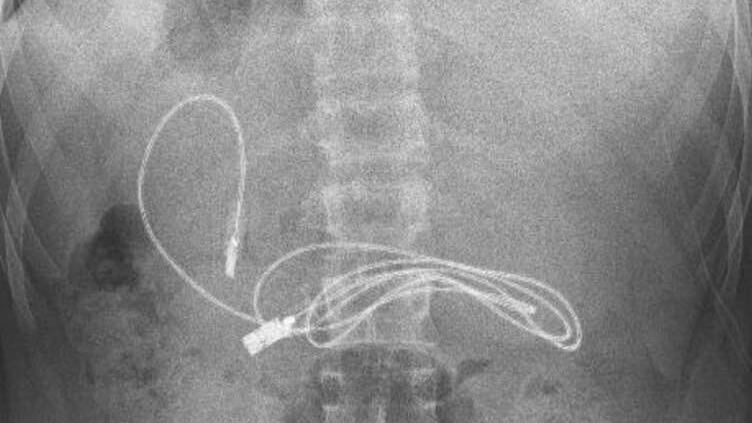

Un joven de 15 años tenía a los médicos desconcertados al ser ingresado de emergencia al hospital. En su interior alojaba un cable USB de carga para teléfono y auriculares conforme informó The Mirror.

El adolescente procedente de Diyarbakir, Turquía, tenía malestar estomacal, dolor abdominal y náuseas por lo que fue llevado directamente a la emergencia de un hospital para su evaluación. Gracias a una radiografía los médicos fueron capaces de descubrir la terrible amenaza que acechaba en el estómago del paciente.

Un cable USB de 1 metro de largo estaba en las entrañas del joven esperando ser digerido por las enzimas digestivas. Rápidamente fue trasladado en una ambulancia al Hospital de la Universidad de Firat en Elazig para la evaluación de un especialista quien iba a tomar la decisión de una cirugía.

Finalmente tras lograr sacar el cable que medía 1 metro de largo, se evidenció un también un lazo para el cabello que fue extraído de igual forma.